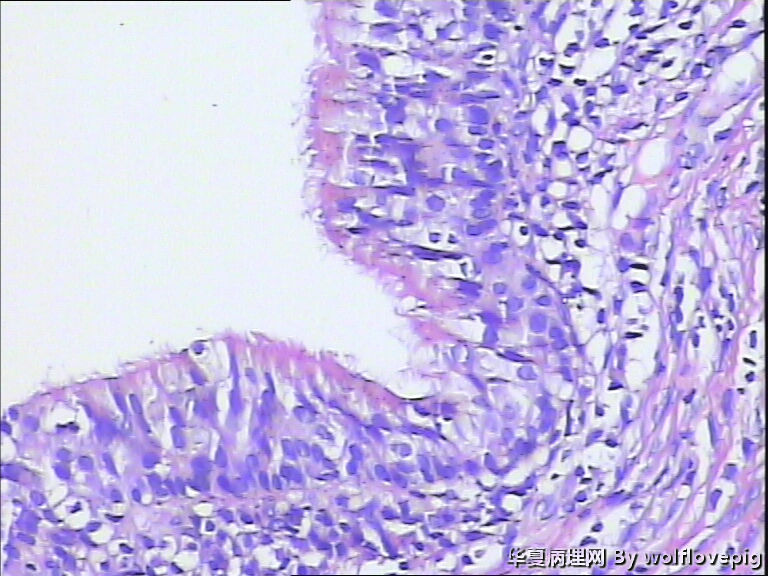

31y,阴蒂附近囊肿2.0*1.5cm

外阴最常见的囊肿是前庭大腺囊肿,囊肿一般衬以移行上皮,常伴有非角化性鳞状化生,也有的呈扁平或立方状,囊肿周边附近可以见到黏液腺体。

此例有点特殊,看到一些纤毛柱状上皮被覆,称为纤毛囊肿,属于前庭大腺囊肿的特殊改变。

前庭大腺囊肿位于外阴后半部,而此例位于阴蒂附近。

泌尿生殖窦起源的外阴囊肿(粘液性和纤毛囊肿)

1,多见于21-30及31-40的多产妇女,病变多位于外阴前庭。

2,组织学上,粘液性囊肿含有与宫颈内膜或阴道腺病一样的粘液性上皮内衬,少数情况下可出现鳞状上皮化生。也有报道有些病例出现纤毛细胞,可以与粘液上皮混合存在。